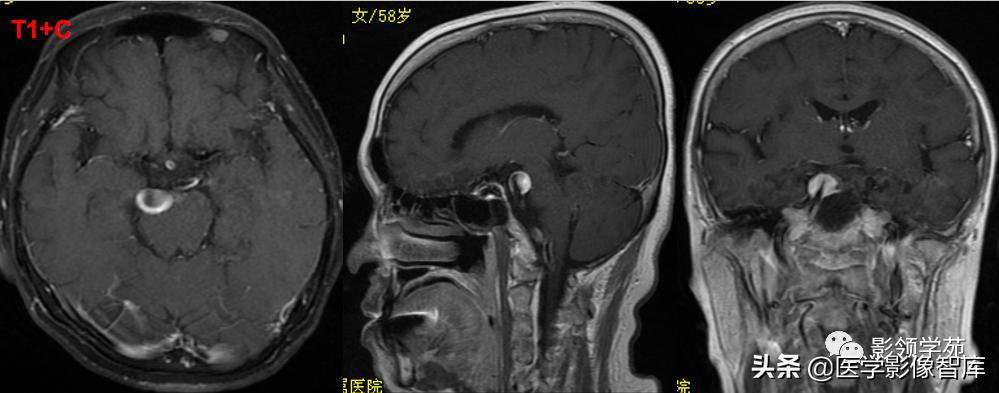

女 58岁,头晕、呕吐,桥脑右前方见一类圆形

高低混合(有血栓)T1及T2信号影,边界清楚、锐利。

明显不均匀强化(瘤内有血栓)。与基底动脉分界不清

头颅CTA:基底动脉起始部血管局部瘤样突起(宽基底),无占位效应。